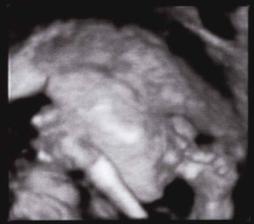

16.9.2008 jsme byli na 3D UTZ byla to nádhera...máme DVD a několik foteček Kubíčka...má už 710 g a měří 30 cm..pořad je to stydlín a nechtěl se nám pořádně ukázat, ale něco málo se paní doktorce podařilo nafotit...hlavně že je všechno v pořádku a Kubík se má čile k světu......